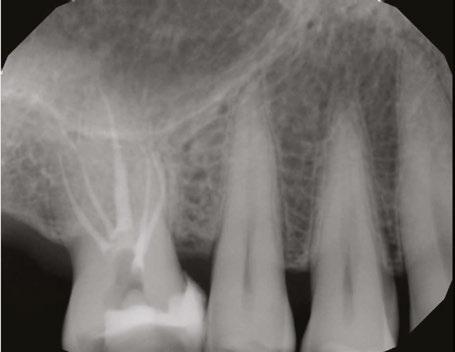

Rotary negotiation as first file to length

Since the beginning of the nickel-titanium (NiTi) rotary file revolution, we have been nearsighted in our expectations of what is possible. For the 30-plus years we have had them in our arsenal (Haapasalo and Shen, 2013), our wonder over what mechanized instrumentation could do for us was limited by the instruments we had at the time, by our conceptual misunderstanding of what is really going on when we use hand files to negotiate small complex canal forms, and by our fear of damaging patient’s teeth. This is completely understandable considering the hidden and tortuous canal paths we encounter when we thread the first file to length (Figure 1). For these reasons, endodontic educators and clinicians came to believe that rotary files should only be used for shaping after a glide path to the terminus has been secured with hand-operated K-files. The realistic concerns were that rotary files would break if used as first file to length; that rotary files used this way would block, ledge, or lacerate apical anatomy; and that rotary files would resist advancing through apical curvatures or beyond apical impediments.

Figure 1: This CT reconstruction of the apical third of a premolar root shows the challenge we often encounter when negotiating root canals to their terminal lengths. In just these two canals, there are five potential impediments to passage of the first negotiating file to length

The other technological advances in rotary file manufacturing have been achieved through improved flute angles, file tip geometry, and cross-sectional core strength (Figure 2). Typical tapered-file flute geometry has flute angles that are tighter at the shank end and more open near the file tip, which contributes to files threading into canals when their shank end flutes approach the orifice level. When that happens, file tips are propelled into the canal; and if they have lesser flute angles, they are more likely to hang an edge, a major cause of file separation. Files with consistent flute angles have greater tip flexibility and strength, while their shank end flutes resist threading and cut more effectively. This flute-angle geometry is imperative when using rotary instruments as FFL (Buchanan, 2019). Without it, breakage too easily occurs, even when using a light touch and a low-torque limit. Adequate core strength is also critical in these narrowest of files; miniKUT Rotary Files have different cross-sectional geometries, depending on their purpose — just two flutes for the larger shaping files to aid cutting function, and four flutes for the smaller EZP rotary negotiating files to add torsional strength (Oh, et al., 2010).

With these engineered solutions that minimize breakage, the only remaining concern about using rotary negotiation as FFL is the possibility of rotary file tips blocking, ledging, or perforating the often tortuous apical regions of canals. This is why file tips on these rotary negotiators are fully radiused. This extremely passive tip geometry not only prevents ledging and perforation, but also actually causes these rotary files to kind of “bump” around impediments that would absolutely be engaged by an unbent hand file. While blockage is always a concern when advancing a file into apical regions of vital canals during negotiation procedures, it turns out that the way hand files function when used in a watch-wind, push-pull manner is actually the cause of most apical blockage.

During the development of rotary negotiation files, the overriding concern was preventing file breakage and avoiding apical blockage, ledging, and perforation (Plotino, et al., 2020). Surprisingly, the outcome was not a technique just as safe as hand-driven K-files. The outcome was a technique that is faster, easier, better, and safer than hand file manipulation.

The simple fact is that rotary negotiation as FFL is superior to hand file negotiation (Figures 3,4 and 6).